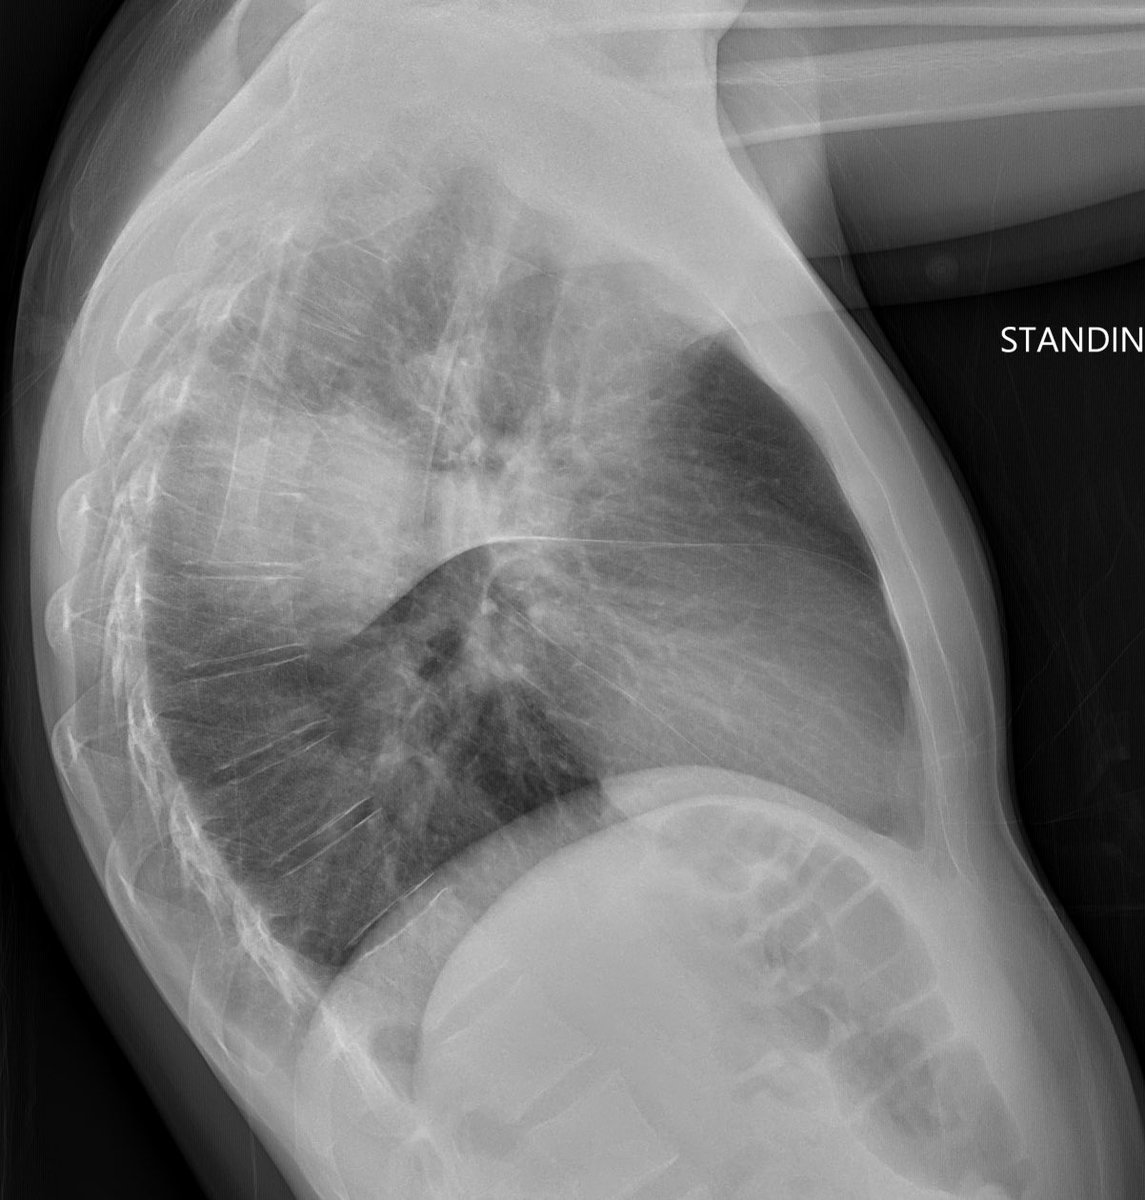

Here are the lung windows, showing pretty typical right lower lobe pneumonia. Does this change your thinking about the first image? Note that there is no interstitial edema in the RLL or pleural effusion.

The patient is a 45 yo male. Acute kidney injury and ? Pneumonia. The first image was at presentation. There is peribronchial consolidation with a nice perilobular appearance peripherally. Looks like organising pna. Cause could be infection, vaping, drug reaction, CTD...